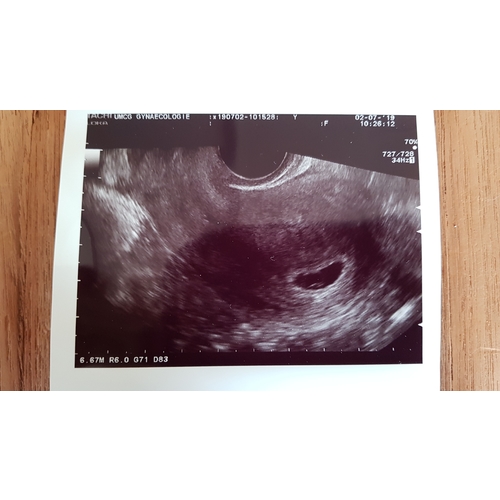

25 mei onze laatste terugplaatsing gehad van 2 embryo's. Gisteren een echo gehad, ben 8 weken zwanger van een tweeling! Mega spannend maar zo zo blij!

Ik ben nu 9 weken zwanger, we hebben al een mooie echo gehad met een kloppend hartje 鈾ワ笍

De uitgerekende beval datum is 15 februari 2020.